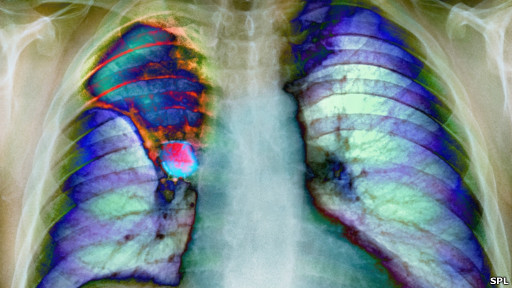

发表在《英国癌症》杂志上的研究报告指出,这或许部分解释了为什么英国的医疗技术和仪器设备先进,而癌症患者存活率却比其他发达国家低。

据学者估计,如果英国的癌症患者存活率能达到欧洲目前最高水平,那么每年有5千多名患者可以保住生命。